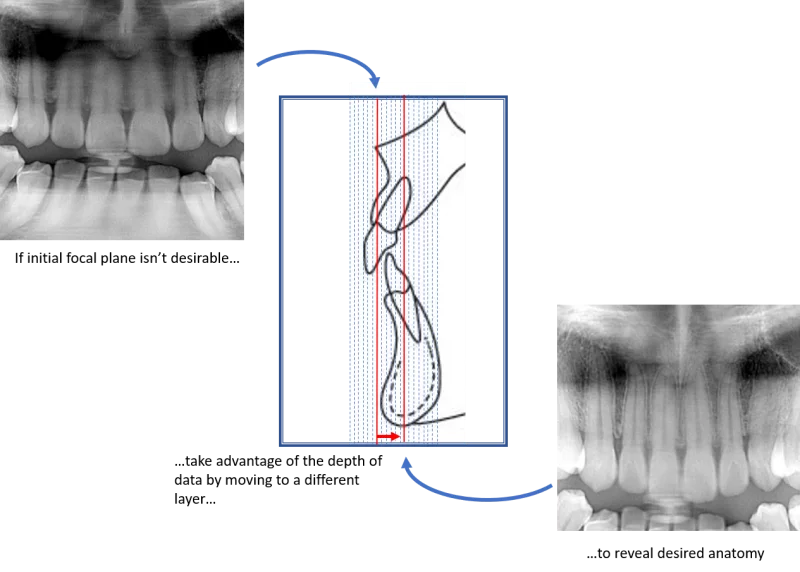

There are dental panoramic systems that are not limited to a single plane, and in fact have the ability to capture many focal troughs with one scan. These systems do this by taking many layers of varying depths in the buccal-lingual direction (some have the ability to capture over 50 layers). Typically, all this data is captured in a single scan, and then each layer is represented as a separate panoramic scan. With all this data, the user has the ability to change which panoramic they would like to see with a click of the mouse.

It’s almost like the dental professional has a stack of many panoramic x-rays with each representing a slightly different view of the anatomy – even those anterior teeth with dramatic emergence profiles.

Here is a section from a typical panoramic radiograph. In it, because of the reasons we just discussed, we can see that the image does not show the apices of the maxillary anteriors very clearly.

If this was taken with a panoramic x-ray that cannot capture multiple focal troughs, then the office is stuck with this image.

Luckily, because the panoramic x-ray performing the scan has the ability to capture many focal troughs, the operator can choose from any of the other panoramic images that were captured in that scan. Very quickly, the operator can select the image that reveals #8 and #9. This image is from the same panoramic scan as the one above. Same patient. Same scan.

However, because this patient was scanned on a panoramic x-ray than can shift the focal trough, these apices can also be revealed. Again, this is done simply by using the data captured during the original scan – no additional scans are needed. You’ll notice that in this “layer”, the crowns are less visible. This is because the maxillary anteriors have dramatic angles to the emergence profiles and therefore the crowns are in a very different layer than the apices.